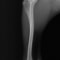

■ 症例22 ポメラニアン 1歳5か月 去勢雄

左後肢の挙上を主訴に来院した。整形学的検査、レントゲン検査より左右の膝蓋骨脱臼(左GradeⅡ〜Ⅲ、右Grade Ⅱ)を認めた。また、脛骨の前方引き出し試験の際に、引き出し兆候は認められないものの、疼痛が認められたため、前十字靭帯の損傷が疑われた。術中における、目視および関節内の操作によって、前十字靭帯の損傷や過伸展といった異常が認められなかったため、膝蓋骨脱臼の整復のみ実施した。手術手技は縫工筋及び内側広筋の解放、脛骨粗面の外側転位、滑車ブロック形造溝術、内外側関節包の縫縮を実施した。本症例は跛行もなく経過良好である。しかし、頸骨高平部の角度(TPA)が 右26.2°、左24.9°であり、解剖学的に前十字靭帯損傷のリスクが高いことから今後の経過に注意が必要である。